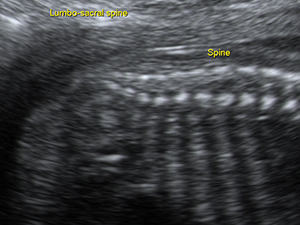

Spine